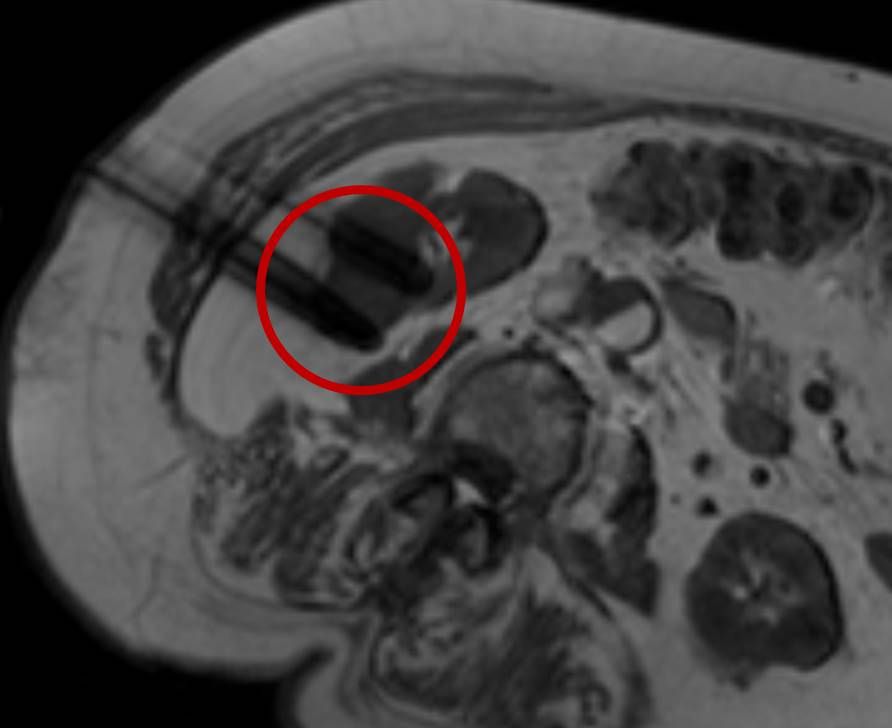

Die minimalinvasive Thermoablation ist auch eine Therapieoption für bestimmte Nierentumore. Damit ein Nierentumor mit einem thermoablativen Verfahren (Radiofrequenzablation oder Mikrowellenablation) effektiv und sicher behandelt werden kann, müssen bestimmte Bedingungen (wie Größe, Anzahl und Lage) erfüllt sein. Dies wird im Vorfeld des Eingriffes mit Kollegen der Urologie besprochen.

Bei der perkutanen Thermoablation von Nierentumoren werden spezielle Applikatoren unter CT- oder MRT Bildgebung in den Zieltumor eingebracht. Durch Hitze wird der Tumor zerstört.